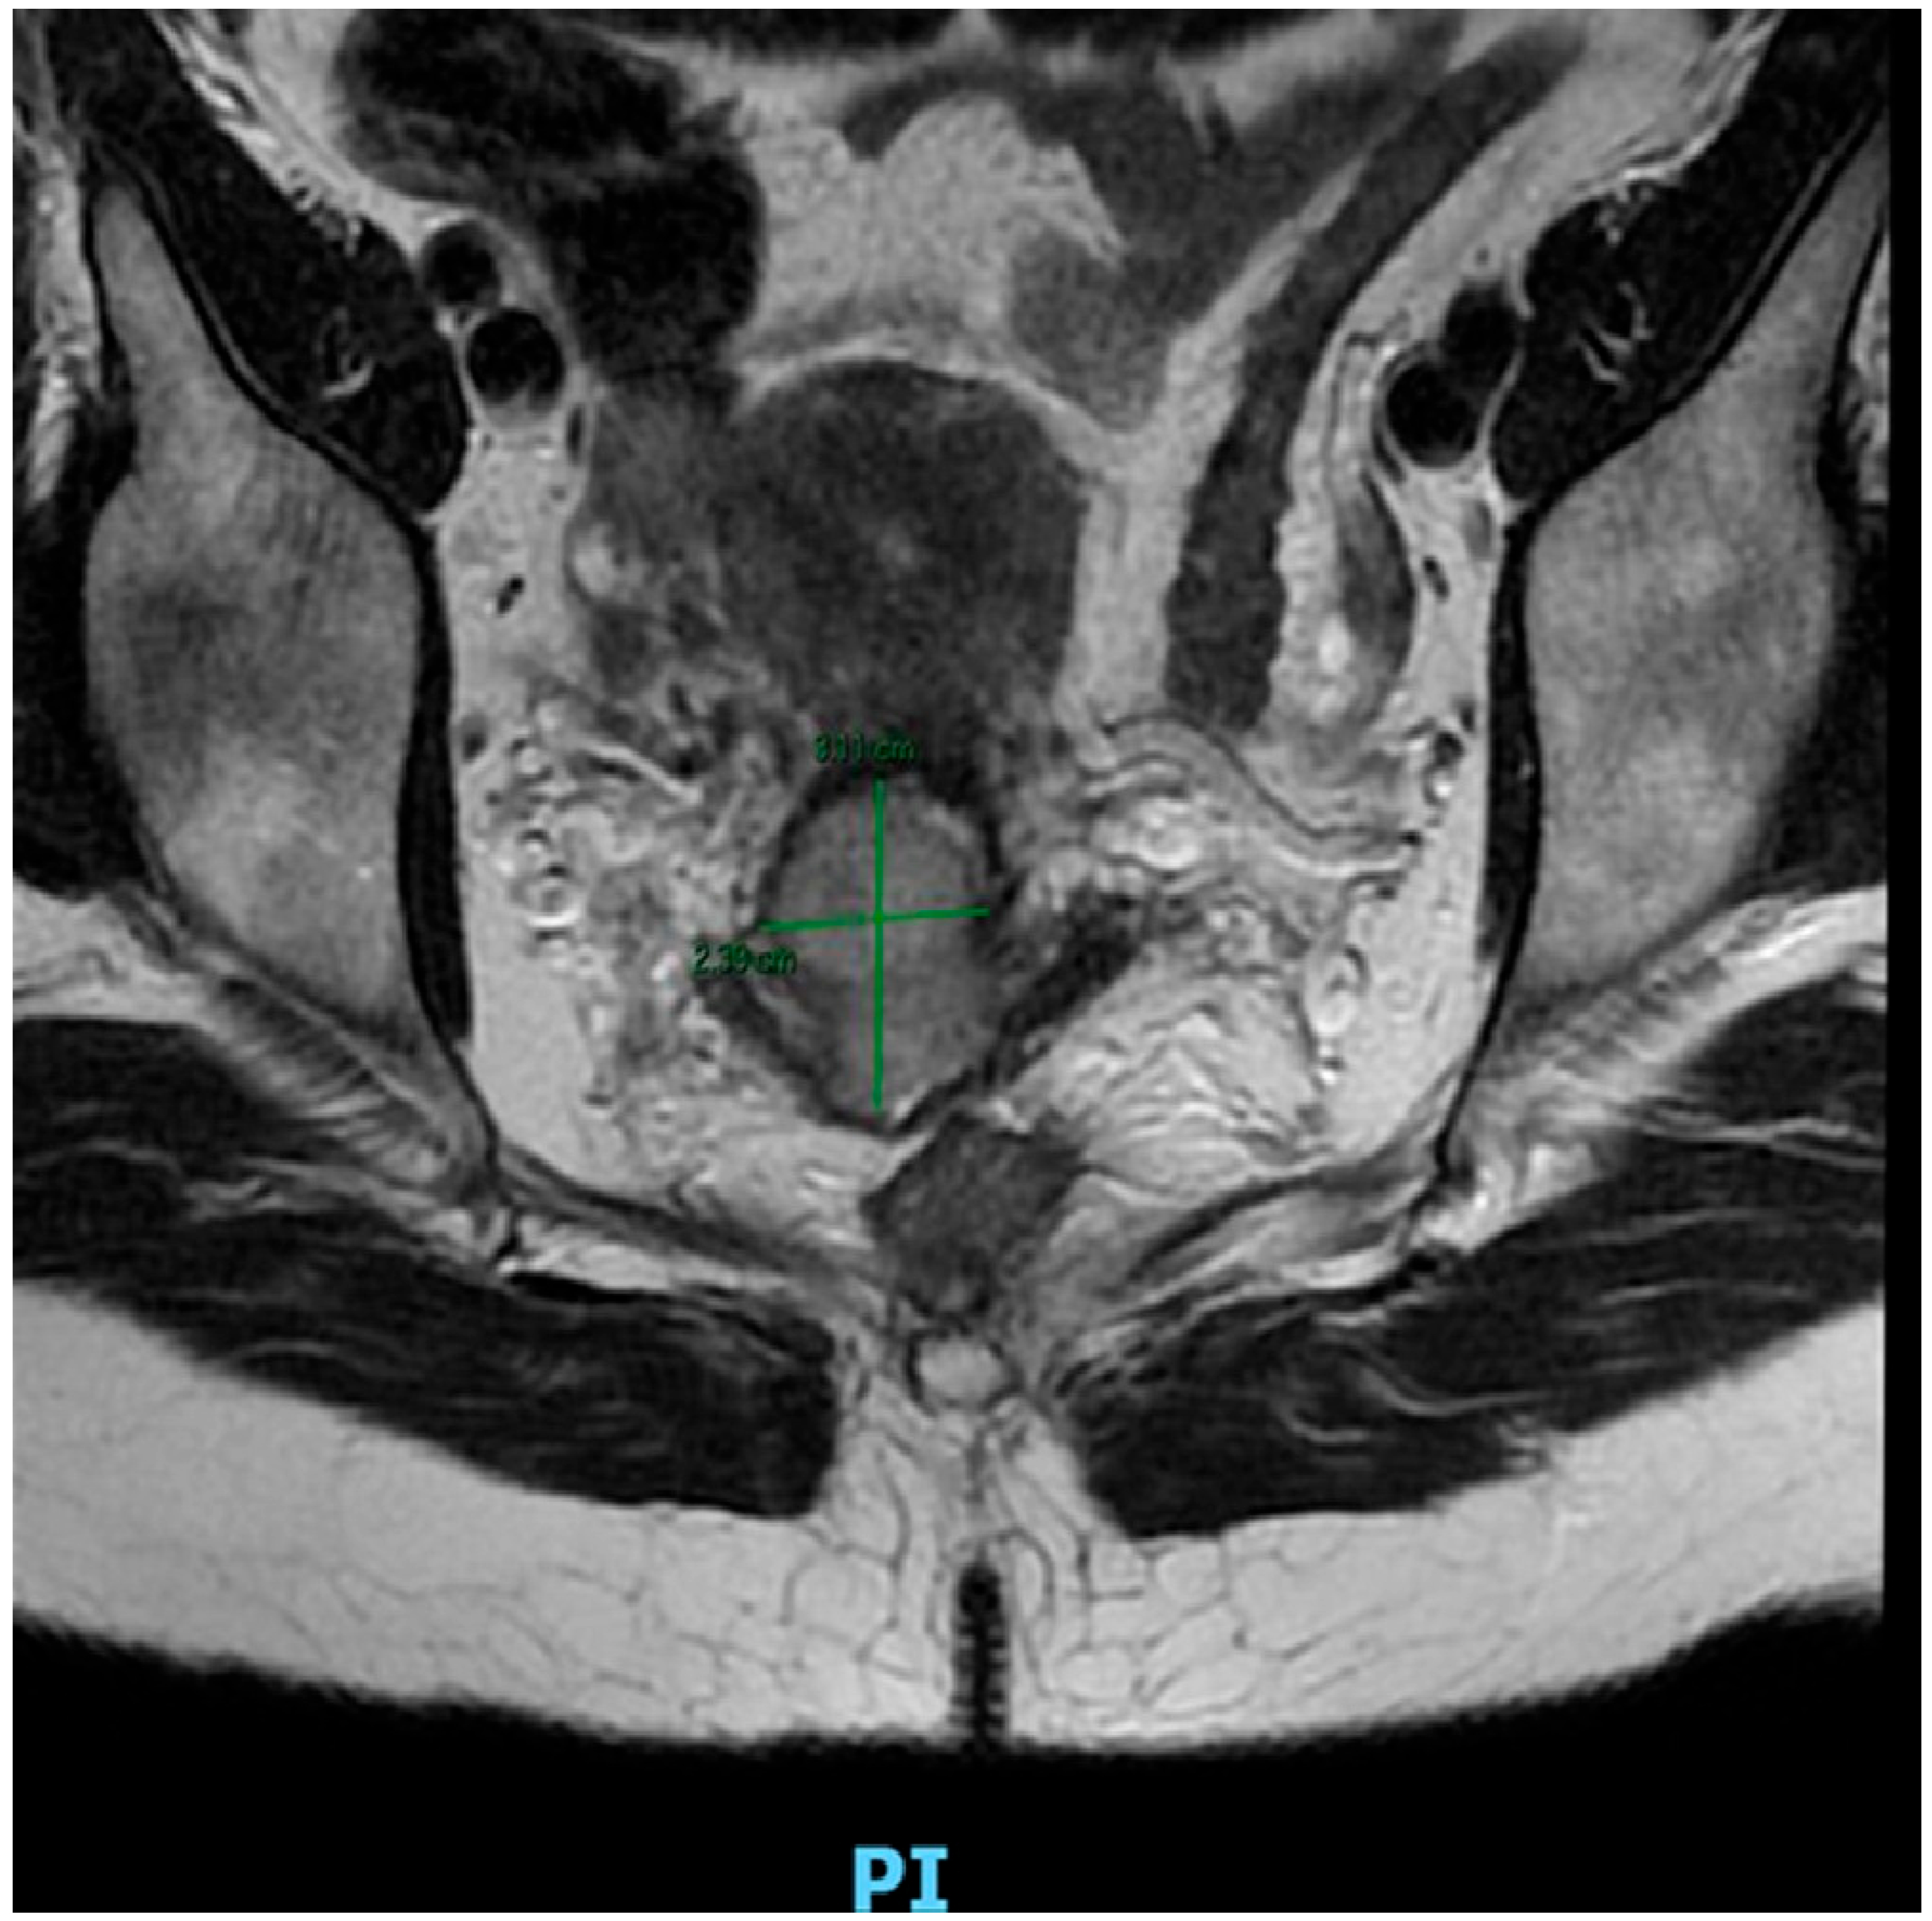

4. Neoadjuvant Chemotherapy